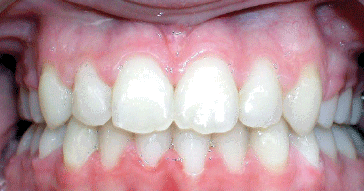

Class II Div II |